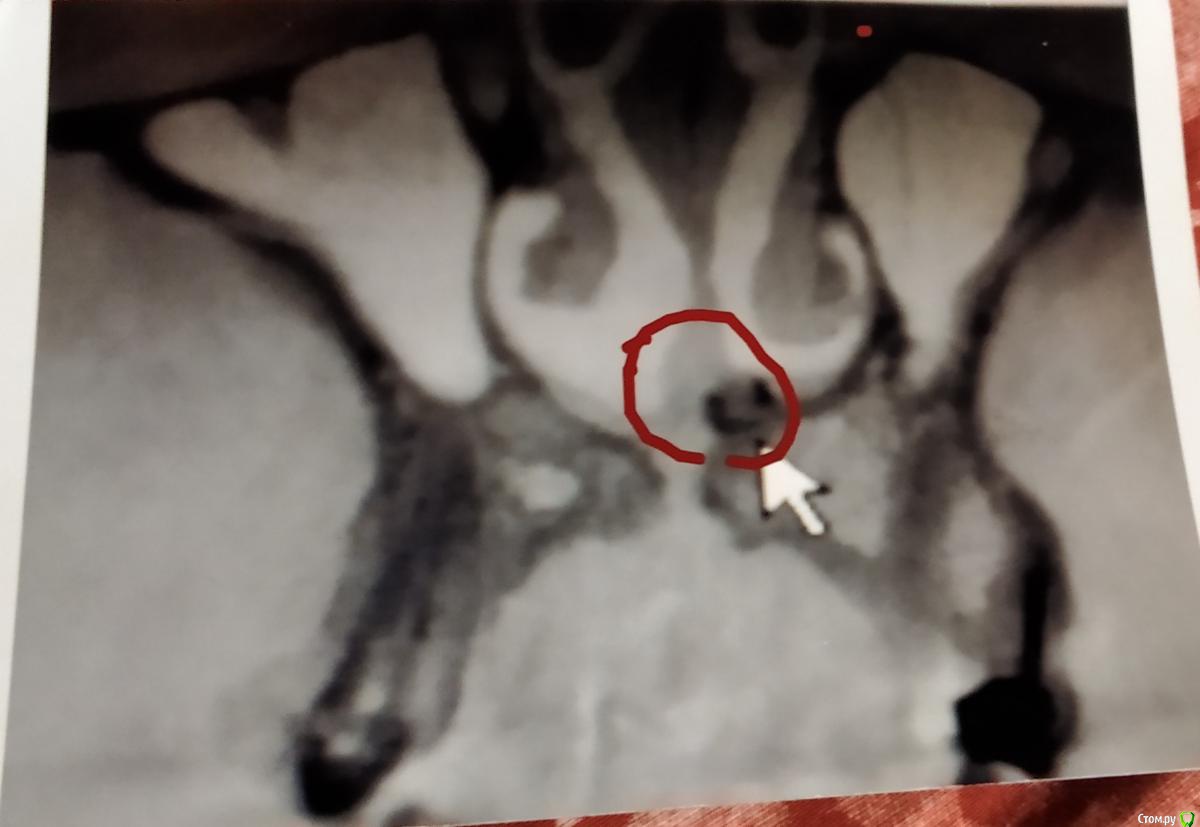

Алексей870 Опубликовано 6 апреля, 2020 Поделиться Опубликовано 6 апреля, 2020 Здравствуйте помогите разобраться образование в верхней челюсти возле резцового канала ..в 2000 году давно мне ставили штифт в верхнюю двоику на снимках этот зуб удален уже и после лечения зуба начало закладывать нос аллергия боли лицевые .сделал КТ челюсти там обнаружилось образование .в 2015 году челюстно лицевом хирург попытался удалить но не долез до него достал только как он сказал вату с челюсти откуда она там взялась...есть мысли что стоматолог что-то мне туда загнал в челюсть .. Ссылка на комментарий

Bier Опубликовано 6 апреля, 2020 Поделиться Опубликовано 6 апреля, 2020 похоже на пломбировочный материал, он высоко, прямо под носом. Но удалить можно Ссылка на комментарий